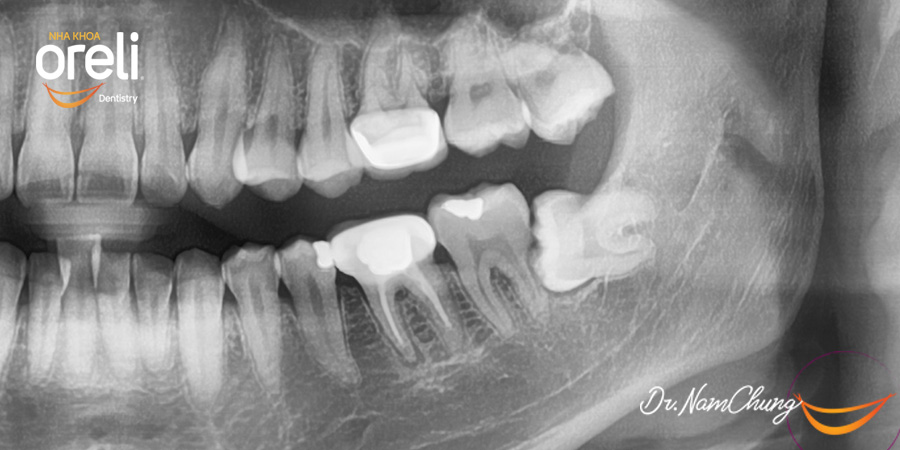

Nhổ răng khôn hàm dưới khó do mọc ngang – Case tại Oreli

Nhổ răng khôn

Mọc lệch